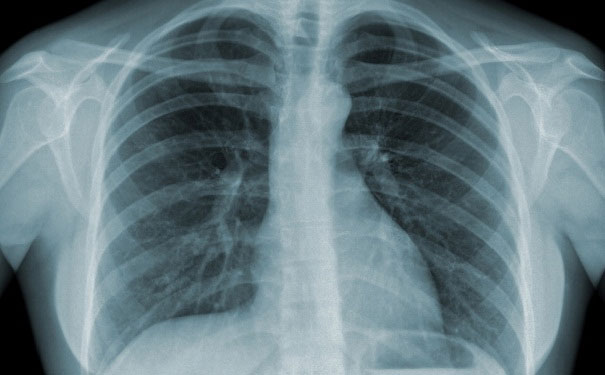

Thông thường để chẩn đoán bệnh lao phổi, các bác sĩ phải chỉ định lấy đờm của bệnh nhân để soi dưới kính hiển vi, nuôi cấy trong phòng thí nghiệm. Việc nuôi cấy này mất nhiều thời gian, có thể vài tuần, có khi vài tháng. Ngoài ra bệnh nhân cũng cần chụp X-quang phổi mới có thể kết luận nhiễm bệnh. ENose có thể khắc phục được những phiền toái này.